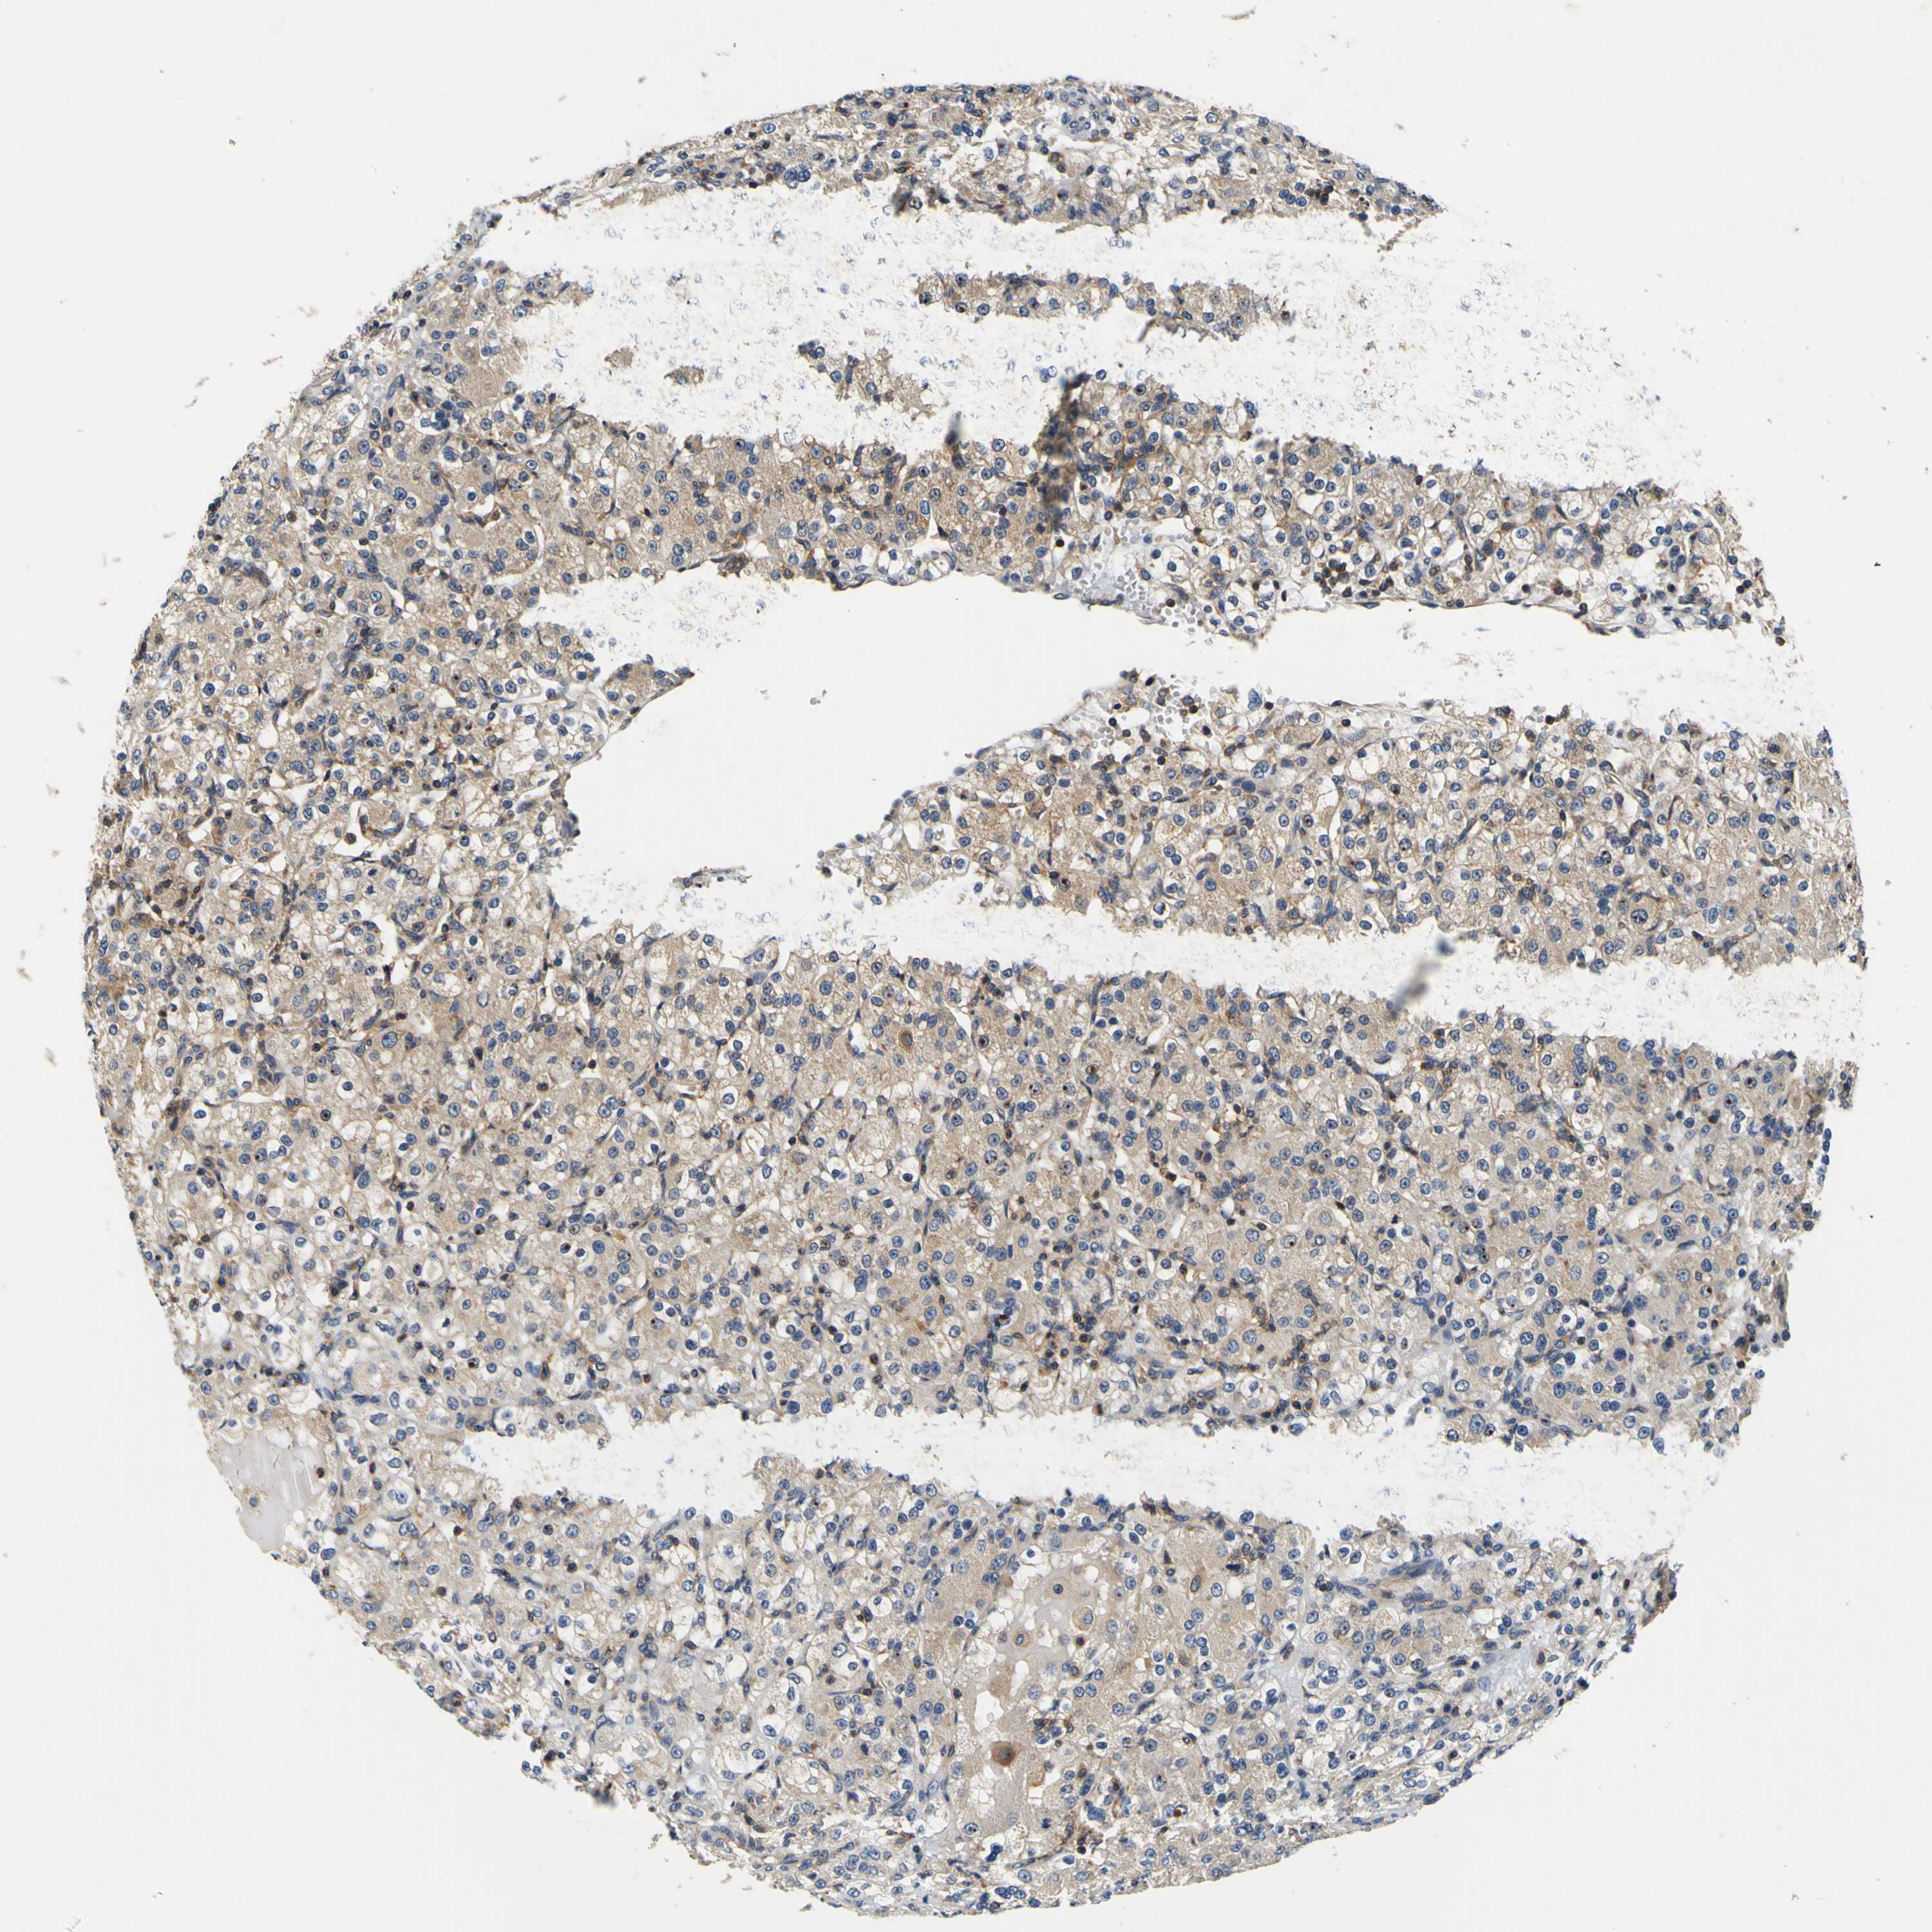

KIDNEY RENAL CLEAR CELL CARCINOMA (TCGA) - Interactive survival scatter ploti

The Survival Scatter plot shows the clinical status (i.e. dead or alive) for all individuals in the patient cohort, based on the same data that underlies the corresponding Kaplan-Meier plots. Patients that are alive at last time for follow-up are shown in blue and patients who have died during the study are shown in red.

The x-axis shows the expression levels (FPKM) of the investigated gene in the tumor tissue at the time of diagnosis. The y-axis shows the follow-up time after diagnosis (years). Both axes are complimented with kernel density curves demonstrating the data density over the axes. The top density plot shows the expression levels (FPKM) distribution among dead (red) and alive patients (blue). The right density plot shows the data density of the survived years of dead patients with high and low expression levels respectively, stratified using the cutoff indicated by the vertical dashed line through the Survival Scatter plot. This cutoff is automatically defined based on the FPKM cutoff that minimizes the p-score. The cutoff can be changed by dragging the vertical line or by entering a cutoff value in the square labeled "Current cut-off".

Under the Survival Scatter plot the p-score landscape (black curve; left axis) is shown together with dead median separation (red curve; right axis). Dead median separation is the difference in median mRNA expression between patients who have died with high and low expression, respectively. It is calculated as follows: median FPKM expression of dead patients with high expression - median FPKM expression of dead patients with low expression. This is intended to aid the user in visually exploring custom cutoffs and the associated p-scores and dead median separation.

Individual patient data is displayed and can be filtered by clicking on one or more of the category buttons on the top of the page. Categories describing expression level and patient information include: high, low, alive, dead, female, male and tumor stages. The scale of the x-axis can be toggled between linear and log-scale by clicking on the "x log" button. Mouse-over function shows TCGA ID, patient information and mRNA expression (FPKM) for each patient.

& Survival analysisi

Kaplan-Meier plots summarize results from analysis of correlation between mRNA expression level and patient survival. Patients were divided based on level of expression into one of the two groups "low" (under cut off) or "high" (over cut off). X-axis shows time for survival (years) and y-axis shows the probability of survival, where 1.0 corresponds to 100 percent.

CNR2 is not prognostic in Kidney Renal Clear Cell Carcinoma (TCGA)

TCGA RNA samplesi

RNA-seq data is reported as average FPKM (number Fragments Per Kilobase of exon per Million reads), generated by the The Cancer Genome Atlas (TCGA) .

Normal distribution across the dataset is visualized with box plots, shown as median and 25th and 75th percentiles. Points are displayed as outliers if they are above or below 1.5 times the interquartile range. FPKM values of the individual samples are presented next to the box plot.

Average pTPM 0.2

Number of samples 521